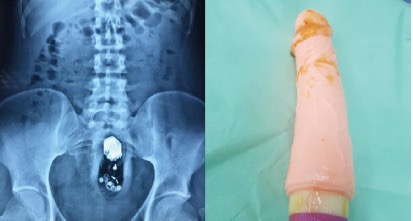

Figure 1.

Рентгенограмма брюшной полости в положении лёжа на спине и вибратор извлечённый из пациента.